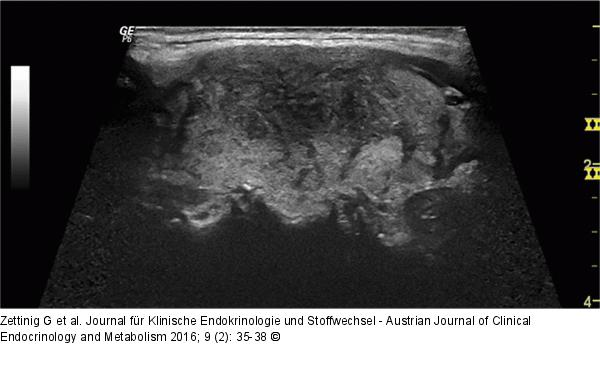

Abbildung 3: Subakute Thyreoiditis Detailaufnahme des linken Lappens zum Zeitpunkt der Erstvorstellung: im Längsschnitt das typische Muster einer subakuten Thyreoiditis de Quervain. |

Abbildung 3: Subakute Thyreoiditis

Detailaufnahme des linken Lappens zum Zeitpunkt der Erstvorstellung: im Längsschnitt das typische Muster einer subakuten Thyreoiditis de Quervain. |